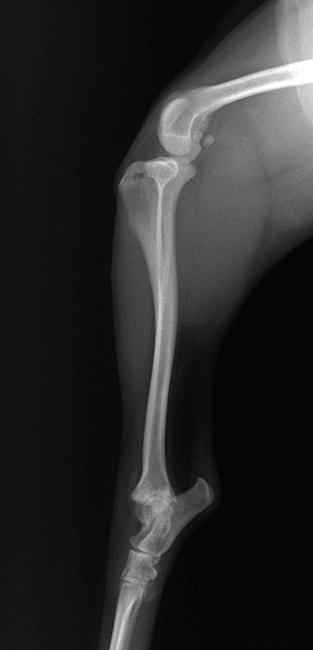

■ 症例24 キャバリア 7か月

左右膝蓋骨内方脱臼(左:グレードⅣ 右:グレードⅢ)

以前から左右後肢の跛行が認められ、整形外科学的検査・レントゲン検査により左右の膝蓋骨脱臼が認められた。症状が重度である左膝の膝蓋骨脱臼整復術を行った。外科手技は縫工筋及び内側広筋の解放、脛骨粗面の外側転位、滑車ブロック形造溝術、内外側関節方の縫縮を実施した。術後一か月時点で、左の膝蓋骨は安定しており経過は良好である。

本症例は成長期における重度の膝蓋骨脱臼であり、術後の再発の可能性もあるため、経過をしっかりと観察していく必要がある。また、今回手術を実施していない右膝に関しても経過を観察し、手術を検討していくこととする。